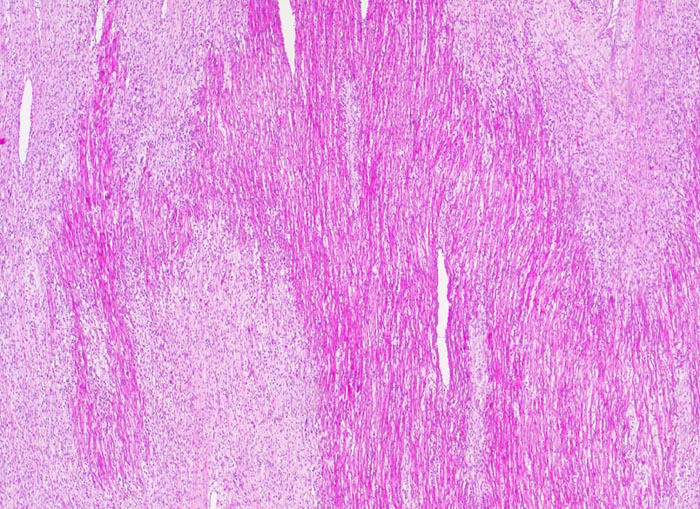

PathoPic ID 3110 - Subakute histiozytäre nekrotisierende Virusmyokarditis

Subakute histiozytäre nekrotisierende Virusmyokarditis

Grobfleckige subakute Nekrosen (helle Areale).

Lymphohistiozytäre interstitielle Pneumonie.

Myokarditis mit kardiogenem Schock.

Trotz negativem Virusnachweis ist der Befund gut vereinbar mit einer viralen Myokarditis.

Histologie

25